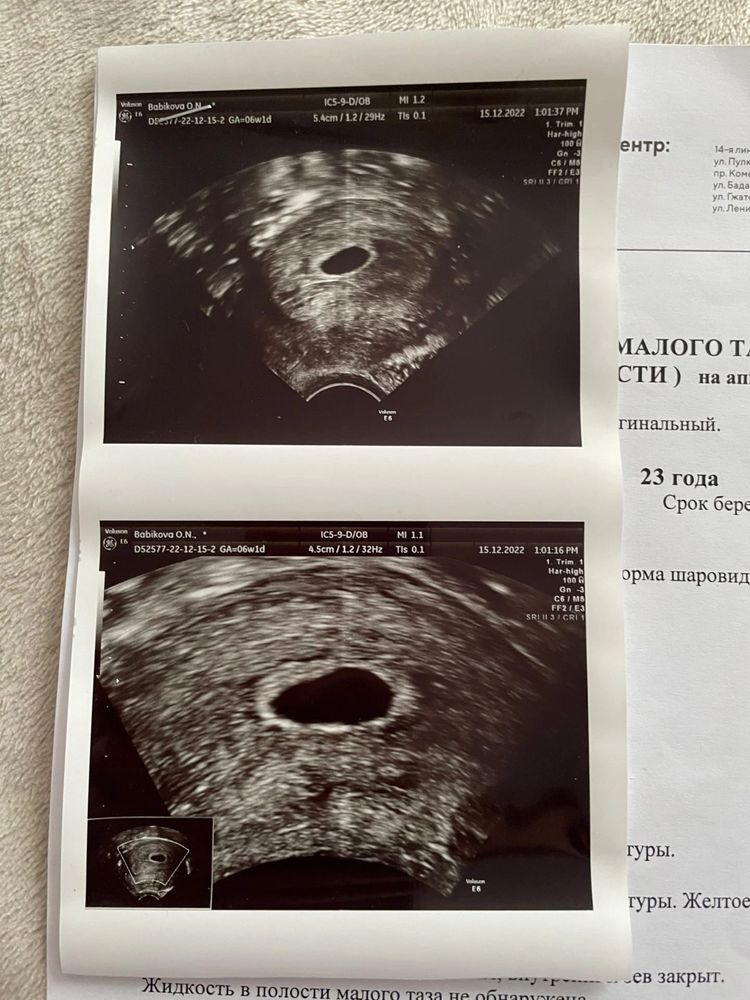

Желточный мешок должен быть виден при размере яйца выше 8 мм. 🤔

Так овуляция наверное поздняя, рановато пошли) не переживайте! Хотя я как паникер, вас понимаю как никто 😁

У меня эмбрион появился в 7 недель. Рановато пошли

А мне сразу даты в глаза бросились))) прошлогоднишняя беременность подумала я и давай читать. Мне кажется рановато, мне врач сказала после 8 недель приходить и мы все точно увидим и услышим

Полина, на самом деле я была у своей г. 7 декабря(среда), она сказала на следующей неделе можно идти, лучше в конце недели. Ну собственно так и получается, что я немного рановато пошла🥹 Надо было спокойно ждать хотя бы до сегодня, или в конце концов на этой неделе идти, но очень не терпелось, хотела подтвердить маточную б😁 В общем то, что теперь, ждать предстоящего узи)) Желаю легких родов🌸😍